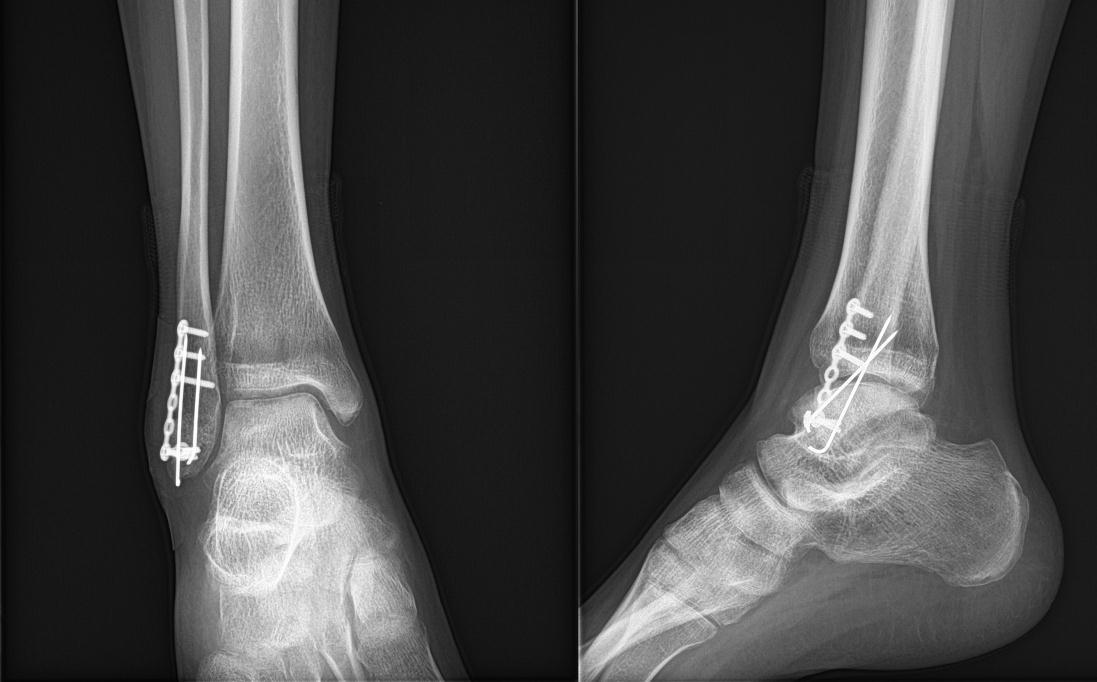

腓骨骨折の手術法 腓骨の長さを正しく保ち、側方転位や回旋転位を残さないことが大切で、スクリューとプレートによる固定を行います。 術後 術後2~3日目から足関節の可動域訓練を開始します。 骨折から1年と1か月、とうとうプレートとボルトを抜く抜釘手術を受けてきました。 骨折の経緯は下記 アイスクライミングで右足果部 腓骨・脛骨骨折 復帰までの記録 ①受傷から手術~退院まで ムカデのおにいさんのブログ アイスクライミングで右足果部腓骨・脛骨骨折 復帰までの記録 腓骨骨折手術後のリハビリ、プレート摘出手術 /5/に階段からジャンプした際に足をひねって着地したことで、左足腓骨を骨折。 (外くるぶしから5センチ程上部分の腓骨が斜め方向へ割れた様に骨折していました。 ) 現在、術後一か月が経ち、手術

鋭意リハビリ中腓骨骨折手術から3週間~ 3/23 手術から3週間経過後の検診。 レントゲン、触診にて問題無しとの事。 支えありで片足立ち可能になったのを確認され、松葉杖の取り外し許可が出る。 可動域は逆の足と比べて7割程、この時期でこれ 2/1128までの医療費のトータルは9万7360点 1点=1円です。 これに負担割合をかけますのでおおよそ30万仕事 高いのか安いのかは別にして 私の場合全身麻酔で脛骨に長い (約15cm) プレートを入れました。 手術で2万6000点 麻酔で7800点で 小計3万4000点の 約10万5000 腓骨はとても細い骨ですが、足関節も構成するためとても重要な骨です。 腓骨骨折の手術やリハビリとは? みなさんの周りにも足首を骨折した方がいらっしゃると思います。 足関節の骨折は脛骨や腓骨のくるぶし部分の骨折です。